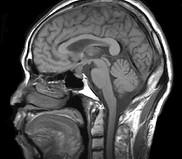

问题 男,头痛7月余,伴左侧面部麻木,疼痛剧烈时伴恶心,无呕吐,请根据所提供图像,选择最可能的诊断()

选项 A.垂体瘤 B.颅咽管瘤 C.生殖细胞瘤 D.脑膜瘤 E.胶质瘤

答案 B